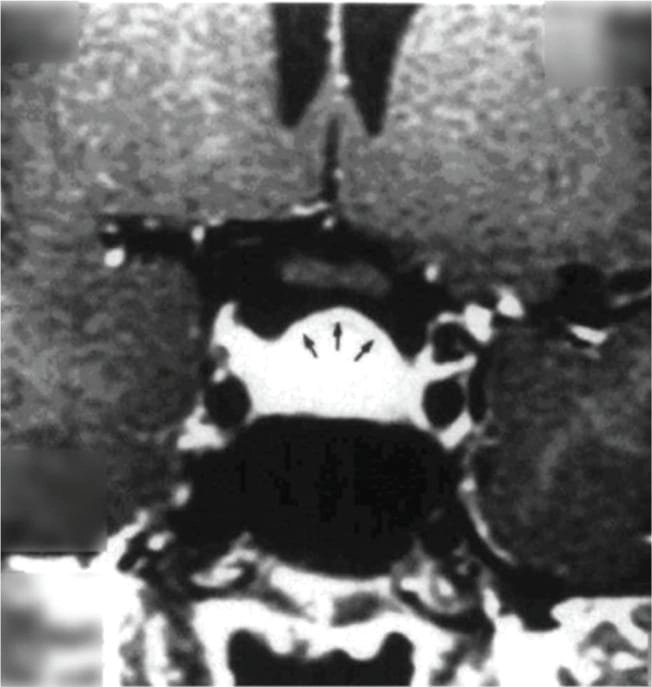

তবে পিটুইটারি হাইপারপ্লাসিয়া দেখা যায় প্রাইমারি গনাডাল, অ্যাডরিনাল বা হাইপোথাইরয়েডিজমের মত এন্ড অর্গান ইনসাফিসিয়েন্সিতে। বিশেষ করে, অব্যবহৃত প্রাইমারি হাইপোথাইরয়েডিজমে পিটুইটারি হাইপারপ্লাসিয়া পূর্বের ধারণার তুলনায় অনেক বেশি দেখা যায়। ২০১৯ সাল পর্যন্ত এরকম ১০৫টি কেস রিপোর্ট করা হয়েছে। এই ধরনের হাইপারপ্লাসিয়া গম্বুজ-আকৃতির (dome-shaped) হয়ে অপটিক কায়াজমাকে চেপে ধরতে পারে, যার ফলে অপারেশনের প্রয়োজন পড়তে পারে—যেমনটা আমাদের তৃতীয় কেসে ঘটেছিল।

কেস ২: একই রকমভাবে, ১৫ বছর বয়সী আরও একজন কিশোরী অল্প উচ্চতা ও টিউমার সন্দেহে নিউরোসার্জেনের কাছে রেফার করা হয়। তার TSH ছিল 100 এবং MRI-তে একটি ডোম-আকৃতির টিউমার দেখা যায়। যাকে ওষুধের চিকিৎসায় সত্য জীবনে ফিরিয়ে আনা হয় এবং ৬ মাসে তার উচ্চতা বৃদ্ধি পায় ও নিয়মিত মাসিক শুরু হয়। MRI-তে টিউমার সম্পূর্ণ অদৃশ্য হয়ে যায়।

MRI-তে এই হাইপারপ্লাসিয়া সাধারণত গম্বুজ-আকৃতির ও সমমিত হয় এবং হোমোজেনাস সিগনাল ইন্টেনসিটি দেখায়, যেখানে সাধারণ নন-ফাংশনাল পিটুইটারি অ্যাডেনোমা নানা আকার ও অসমতা নিয়ে দেখা যায়।

তাঁর দাবি, MRI-তে ‘DOME Sign’ থাকা এবং TSH বাড়তি থাকলে, সেটি হাইপোথাইরয়েডিজম-জনিত হাইপারপ্লাসিয়ার সম্ভাবনার কথা নির্দেশ করে এবং এই রোগীদের শুধুমাত্র লেভোথাইরক্সিন দিয়ে চিকিৎসা করলে পূর্ণ আরোগ্য সম্ভব।